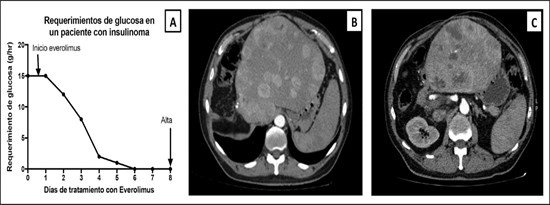

Paciente masculino de 35 años de edad, con antecedentes de tabaquismo, etilismo, consumo de sustancias psicoactivas. Ingresa al hospital de Sanatorio Franchin el 24 de mayo de 2024, donde se constata hipoglucemia severa con buena respuesta al glucosado hipertónico endovenoso. Al examen físico con la típica tríada de Whipple, dado por síntomas neuroglucopénicos de alteración del estado de conciencia, glucemia de 25 mg/dl y alivio sintomático después de la administración de glucosa. El paciente recupera el estado de conciencia y refiere dolor abdominal a nivel de epigastrio, por lo que se le realiza ecografía abdominal, donde se evidencia lesión nodular hipoecogénica en cuerpo del páncreas. Por esta razón se pasa al paciente a tomografía, donde se constata una formación nodular a nivel del cuerpo del páncreas, que presenta un ávido realce en fase arterial con homogeneización de la lesión en tiempo tardío.

Ahora bien, como se mencionaba al principio, el estudio ecográfico es de muy baja sensibilidad y se identifique o no la lesión por este estudio, nuestro siguiente paso en el algoritmo diagnóstico de esta lesión es la tomografía. Esta es la prueba no invasiva inicial, con una sensibilidad del 63% al 83%, y detecta del 70% al 80% de los tumores. Esta debe realizarse como un estudio trifásico: fase arterial temprana a los 30 segundos, fase venosa a los 70 segundos, fase tardía de 3 a 5 minutos. La característica de estos tumores por tomografía es que se presentan como una masa sólida que tiene un ávido realce en la fase arterial, cuyo realce se mantiene y se observa más tenue en la fase venosa y en los tiempos tardíos la lesión se homogeniza.

Para mi caso, y dando una visión general de los métodos de imagen no invasivos en esta revisión retrospectiva, solo a uno de los pacientes se le detectó la lesión por ecografía, donde se visualizó una lesión nodular hipoecogénica en el cuerpo del páncreas. A los demás pacientes se les detectó la lesión por tomografía en estudio trifásico, donde resaltan las características ya descritas por la literatura de lesiones hipervasculares con intenso realce en fase arterial, localizadas en diferentes partes del páncreas, como cabeza, cuerpo y cola.